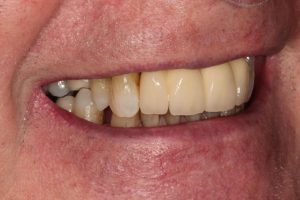

Full Mouth Rehabilitation

Full mouth Treatment – missing upper front teeth and mispositioned implants in the Lower left side meant planning was key here to get the desired result. Implants were placed to replace the missing teeth, veneers/crowns on the remaining upper teeth allowing an improvement in overall shape and colour, and the implant crowns on the lower left were change to bring into the line of the bite.